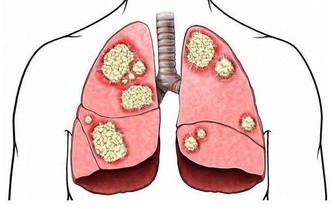

並對賁門癌、肺癌、吐血有明顯的療效。